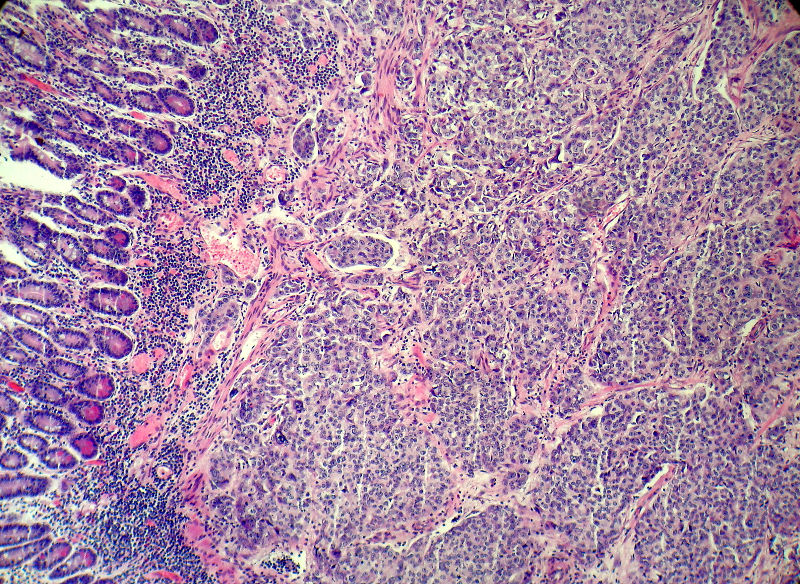

男,82岁,小肠穿孔紧急手术。

大体,小肠一段,长约60厘米,与粘膜面可见三个溃疡型肿物,肠系膜淋巴结肿大。

肿瘤呈巢片状分布,细胞大小相对一致,胞浆丰富,胞核呈细颗粒状,可见小核仁,血管较丰富,考虑神经内分泌肿瘤,加做免疫组化(Ki67、Syn、NSE、CgA、CD56)分级。